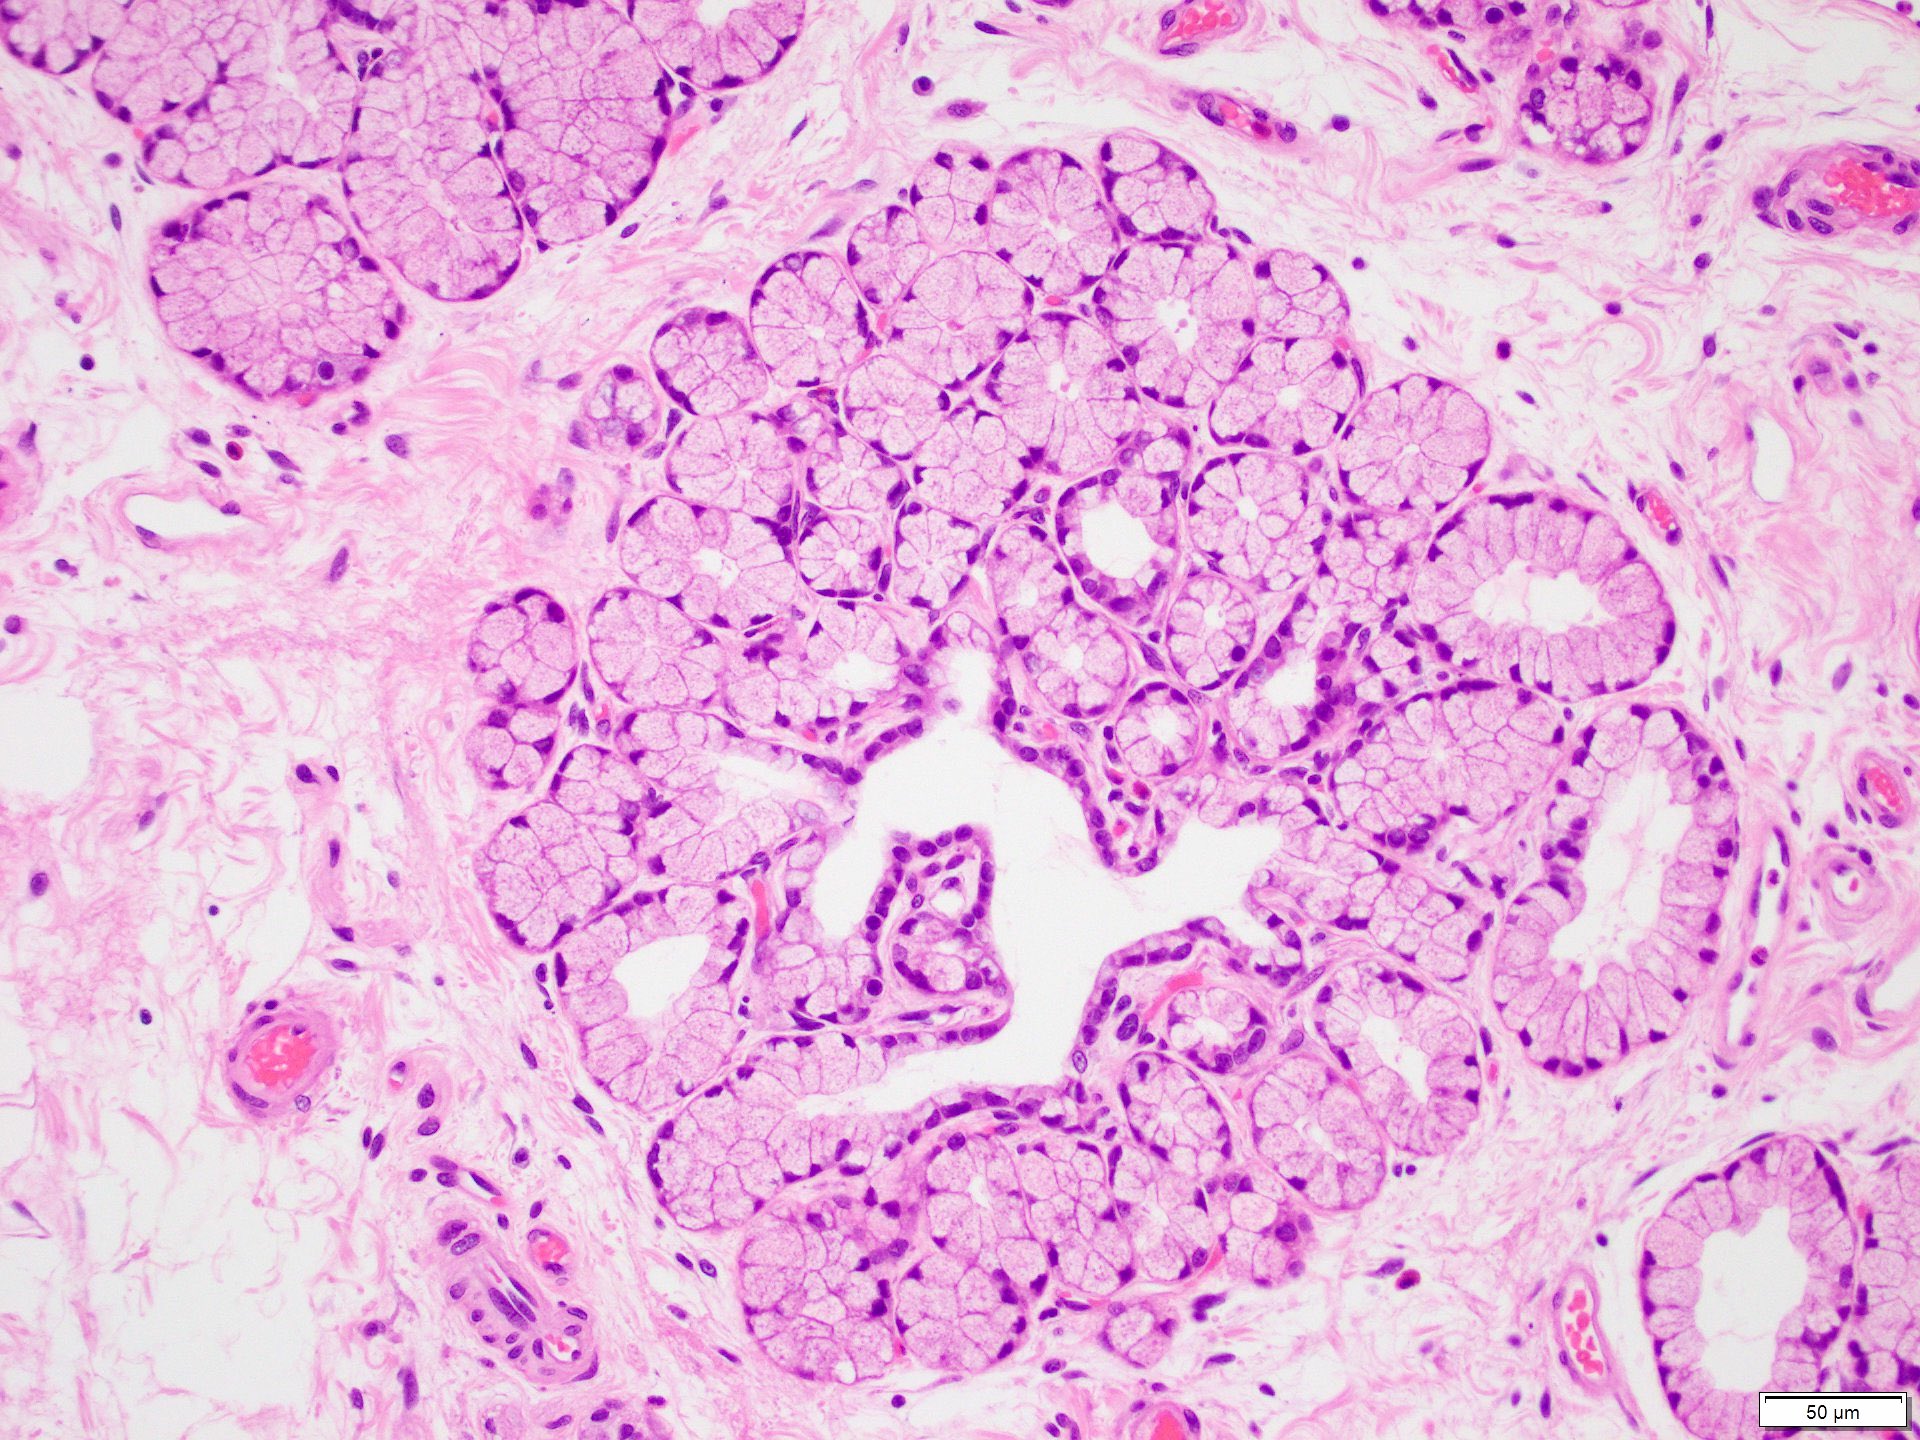

Product Name: Brunner glands in stomach store

Description store, Histology at SIU store, Brunner s glands Wikipedia store, Brunner s glands Wikipedia store, Brunner s gland store, Description store, Histology at SIU store, Brunner s Glands Vital Digestive Secretions CHOQ store, Brunner s gland hamartoma and hyperplasia store, Brunner s glands are found in the submucosa of the duodenum but store, Dictionary Normal Duodenum The Human Protein Atlas store, Histology at SIU store, Brunner s gland hyperplasia was found on histopathology from a store, Description store, Webpathology A Collection of Surgical Pathology Images store, Brunner Gland an overview ScienceDirect Topics store, Surgical management of giant Brunner s gland hamartoma case store, Pathology Outlines Brunner gland hyperplasia store, Description store, Brunner s Gland Hyperplasia A Rare Cause Of Gastric Outlet store, Pathology Outlines Brunner gland hyperplasia store, Brunner s gland YouTube store, Figure 2 from Brunner s Gland Hyperplasia A Rare Cause Of Gastric store, Brunner s Gland Hamartoma Over Treatment of a Voluminous Mass store, brunner s glands secrete a bicarbonate buffer to regulate pH of store, Saving from unnecessary pancreaticoduodenectomy. Brunner s gland store, Gastric outlet obstruction caused by Brunner s gland hyperplasia store, Underlying risk factors of Brunner s gland hamartoma Download store, A giant Brunner s gland hamartoma being treated as a pedunculated store, Figure 2 from Brunner s gland hyperplasia an unusual cause of store, Block10 1 Fig 9. 93W4522 Stomach and Duodenum ls H E store, Brunner s Gland Hyperplasia and Hamartoma Imaging Features with store, Medbullets Brunner s glands are found only in the Facebook store, Clinics and Practice Free Full Text Multiple Adenocarcinomas store, Pathology Outlines Brunner gland hyperplasia store, Brunner glands Radiology Reference Article Radiopaedia store, Brunner s Gland Hyperplasia and Adenoma Associated with Colic in store, Match the following Gland Location 1. Brunner s gland i Stomach store, Ileum is characterised by the presence ofa Brunner s glands and store, Webpathology A Collection of Surgical Pathology Images store, Histology at SIU store, INSIGHTS INTO THE DEVELOPMENT OF GASTROINTESTINAL BRUNNER S GLANDS store, Figure 3 from Gastric Outlet Obstruction Caused by a Triple Lesion store, Brunner s Gland Hyperplasia and Hamartoma Imaging Features with store, Pathology Outlines Brunner gland hyperplasia store, Brunner s Glands Hyperplasia Diagnosis with EUS F store, Full Text Large Brunner s Gland Hamartoma A Case Report store, brunner glands Diagram Quizlet store, Brunner Gland Hamartomas Uncommon Presentations and Endoscopic store, Duodenal Ulcer II The Gastrointestinal Atlas store.

Brunner glands in stomach store